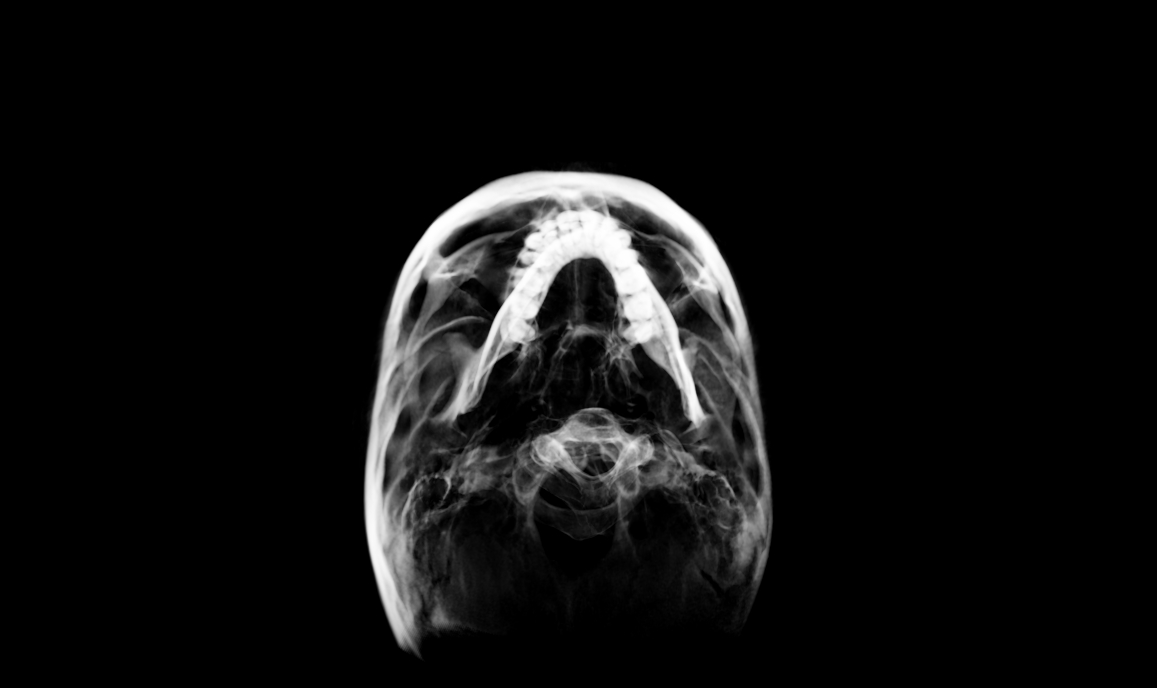

CBCT:

• Head Posture: Forward Head Posture

• Facial Features: Allergic Eye Shiners, Excessive Buccal Corridors

• Vertical Upper Jaw Position: Mild Vertical Maxillary Excess